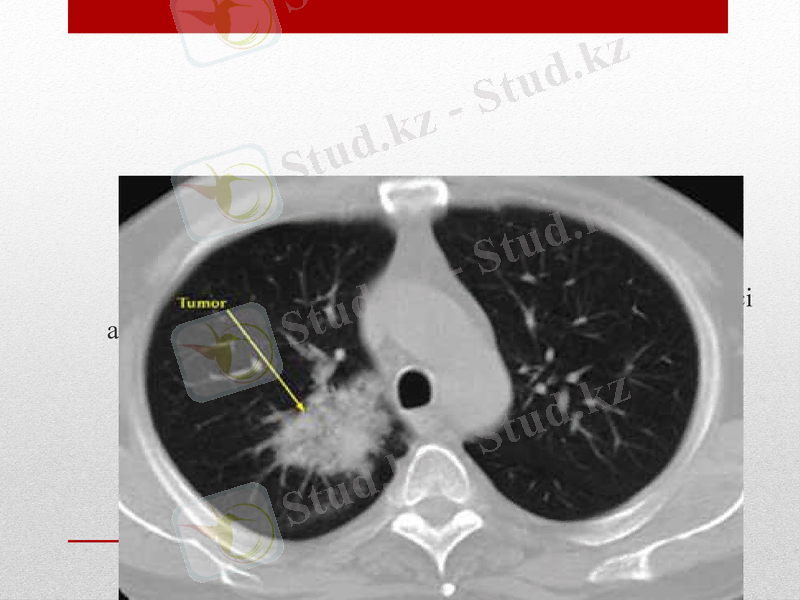

Компьютерлі томография

Бронхтардың, лимфа бездерінің, ісік түйінінің көлеңкесі айқын көрінеді.